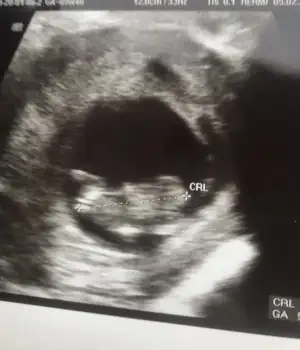

Banada bakarmısınız 12+2 günlükErkek ve kız için 11 yada 12 hafta usg görüntüsü olmalı açıklamalar asagıda yazıyorrabbim herkesin gönlüne göre nasip etsin inşallah .. ecmain

Erkek gibi 12+ da paylaşın emin olamadımKızlar 11+5 sizce ne cinsiyeti ben çıkıntıyı anlayamadım lütfen söyleyin çatlıcam meraktan

Kız gibi13 haftalık olduk sizce ne olabilir cinsiyeti çok çok merak ediyorum